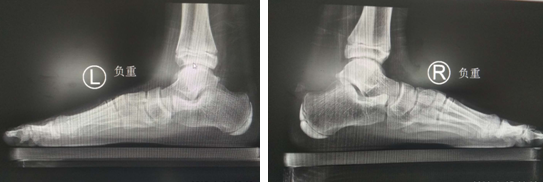

术前X线照片

原来,馨馨是徐主任半年前接诊的患者,当时馨馨的主要问题是走路“外八字”,孩子走路时间长了,就会足部疼痛。经徐主任检查后确诊为:先天性扁平足。当时馨馨处于上学期间,徐主任为馨馨定制了鞋垫,改善症状,建议在寒假期间来做微创手术。

扁平足:又称平足症,指足弓低平或消失,患足外翻,站立、行走的时候足弓塌陷,引起足部疼痛的一种畸形。

扁平足的微创手术是通过小切口,放置一个稳定器(螺钉),将足弓撑起来,随着儿童年龄的增长,骨骼进行塑形改造,重建儿童足弓。该手术操作简单、创伤小、并发症少、疗效较为确切满意。

儿童患者放置距下关节稳定器治疗平足症的适合年龄为6--12岁。随着机体的塑形改造,可使儿童重建足弓,即使取出稳定器,仍能终生保持足弓。